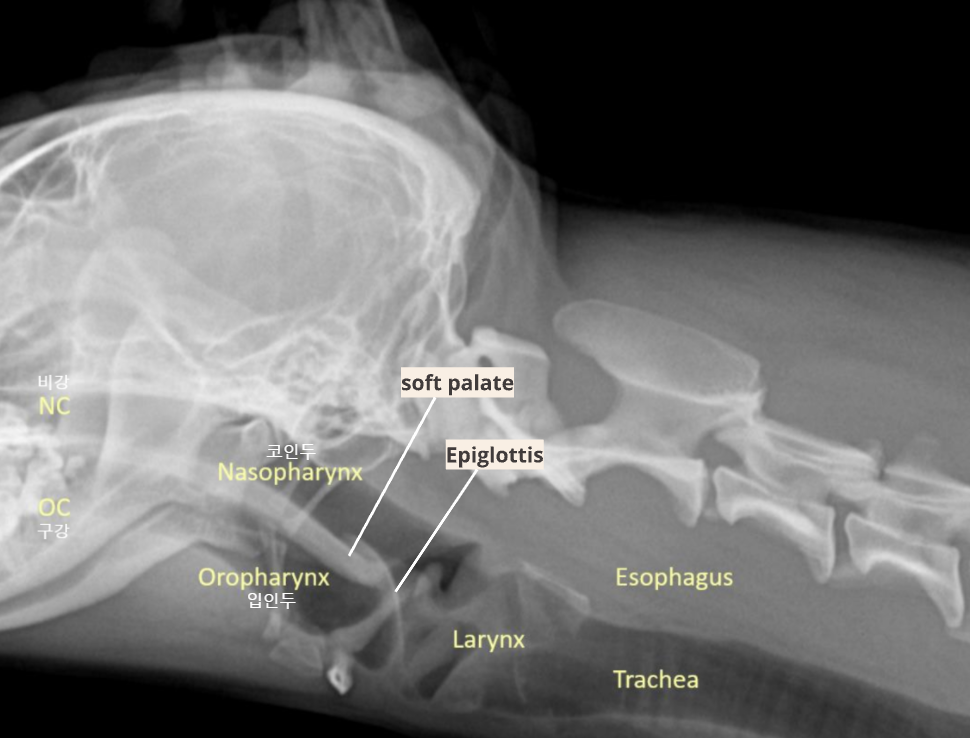

| Upper respiratory system |

|---|

![]() |